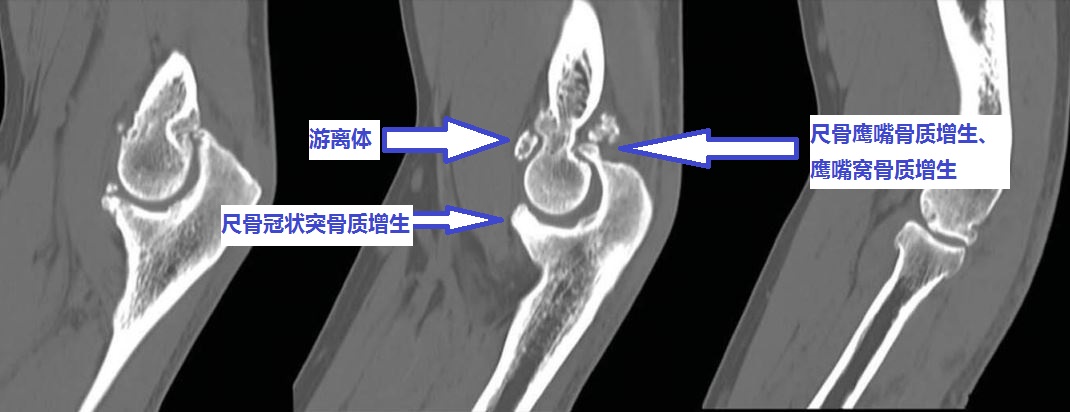

为什么您的肘关节伸不直呢?

伸不直往往是因为:1、尺骨鹰嘴骨质增生;2、肱骨远端后侧的尺骨鹰嘴窝骨质增生填塞;3、肘关节前侧的关节囊挛缩;4、肘关节内的游离体卡住了;等等。

为什么您的肘关节屈不下来呢?

屈不下来往往是因为:1、尺骨冠状突骨质增生;3、肱骨远端前面的尺骨冠状突窝骨质增生;4、肘关节后侧的关节囊挛缩;等等。